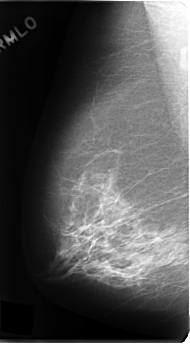

C_0191_1.RIGHT_MLO

RIGHT_CC LINES 4832 PIXELS_PER_LINE 2648 BITS_PER_PIXEL 12 RESOLUTION 50 NON_OVERLAY

RIGHT_MLO LINES 4808 PIXELS_PER_LINE 2648 BITS_PER_PIXEL 12 RESOLUTION 50 NON_OVERLAY